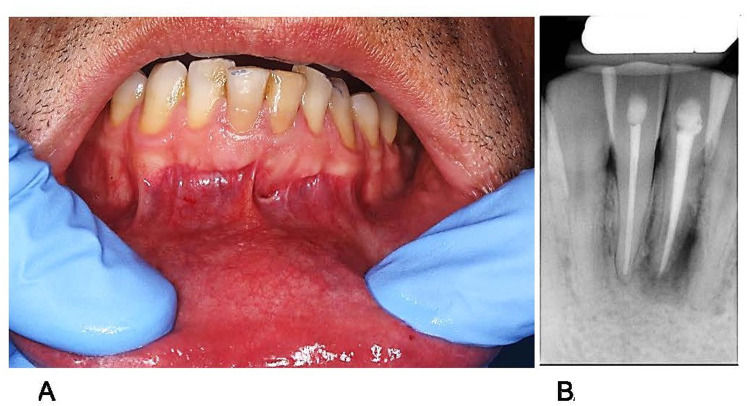

Case presentation: A 42-year-old man presented with persistent sinus tract formation. Despite non-surgical retreatment, the symptoms persisted, and radiographic evaluations, including cone-beam computed tomography, revealed a periapical radiolucency with radiopaque convexities in the apical third of the root. Intentional replantation (IR) was performed to allow direct clinical access for diagnosis and management. Upon extraction, a dark brown, calculus-like deposit firmly attached to the external root surface was observed. After deposit removal, root-end resection and retrograde filling were performed before replantation. Follow-ups at 3 months and 1 year revealed complete healing of the sinus tract and significant radiographic improvements. This case highlights the role of extraradicular biofilms and apical mineralized deposits in persistent periapical inflammation. Sinus tracts may facilitate mineral-ion migration and contribute to the formation of extra-radicular calculi. Mineralized biofilms may not be resolved using orthograde approaches, necessitating surgical intervention.

Conclusion: IR enables thorough inspection and removal of radicular deposits, offering a minimally invasive and successful alternative to conventional apical surgery. The findings in this case are consistent with those in previous studies suggesting the usefulness of IR for managing refractory periapical lesions caused by extraradicular infections or mineralized biofilms.